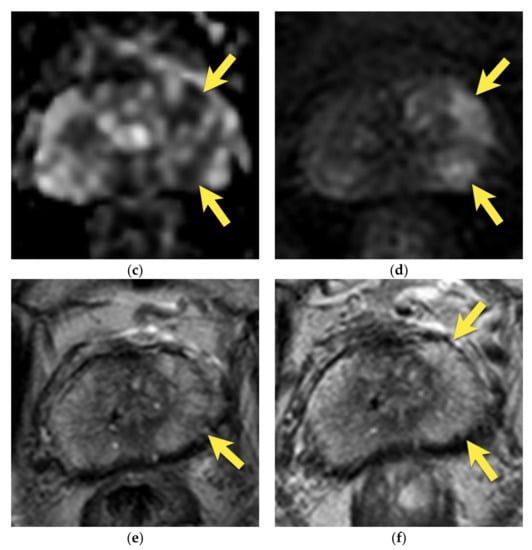

8. Post-Biopsy Hemorrhage